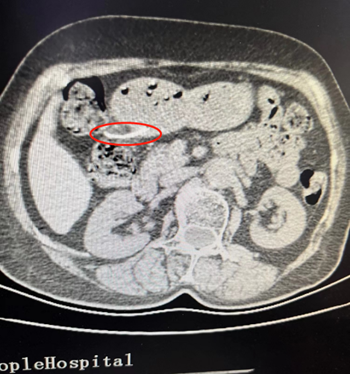

据悉,76岁的李奶奶因反复上腹部疼痛难忍来院就诊,经过一周治疗后,情况并未好转,于是再次来院检查,江西省人民医院进贤医院党委书记邹清水关注到这一不寻常情况,安排副院长曾炳亮再次检查,行胃部CT提示:胃窦内条状高密度影,提示异物影可能;并向家属解释怀疑胃内有金属异物(大约50毫米),考虑患者病情随时可能加重,决定进行手术治疗。副院长黄勤立即联系省人民医院消化内科副主任医师曾俊连夜赶往进贤医院与影像科、普外科、麻醉科、手术室多学科联合会诊,反复研究讨论患者情况,经过详细的检查和评估,为减少患者手术创伤,减轻病人痛苦,与家属积极沟通后建议先行胃镜下异物取除术,如异物无法从内镜下取出,则改行腹腔镜下腹腔异物取出术。

5月12日上午,在取得家属同意,完善术前准备后,省人民医院曾俊、进贤医院副院长许新平带领普外科负责人徐小云及其团队,在麻醉科、手术室全力配合协作下行“胃镜下异物套取术+腹腔镜下腹腔异物取出术+空肠营养管置入术”,胃镜检查发现异物完全刺入胃壁,内镜下无法取出。遂改行腹腔镜下手术,手术中发现胃前壁异物刺出,局部大网膜包绕,局部已形成了脓肿,分离后发现“注射针头”样异物,术中顺利取出异物并修补胃穿孔,手术配合紧密。

术后测量“注射针头”样异物约50mm长。术后了解情况得知,李奶奶在家吃韭菜时误食进入体内。经过科室医护人员悉心照料后,康复出院!